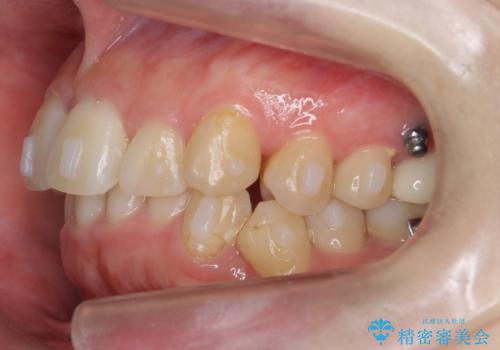

奥歯を後ろに送るために、矯正用ミニスクリューを使用しました。

また、下顎の前歯から奥歯にかけて歯を少し削るIPRを行なっています。

矯正治療開始前におすすめした根管治療の場所がありましたが、患者様の強いご希望により、無視して矯正を開始しました。矯正開始後に、痛みが出て他院で根管治療を行なった影響で、矯正治療を一時中断しました。その影響で矯正治療の期間は長引きましたが、実質一年台で終わったと思います。